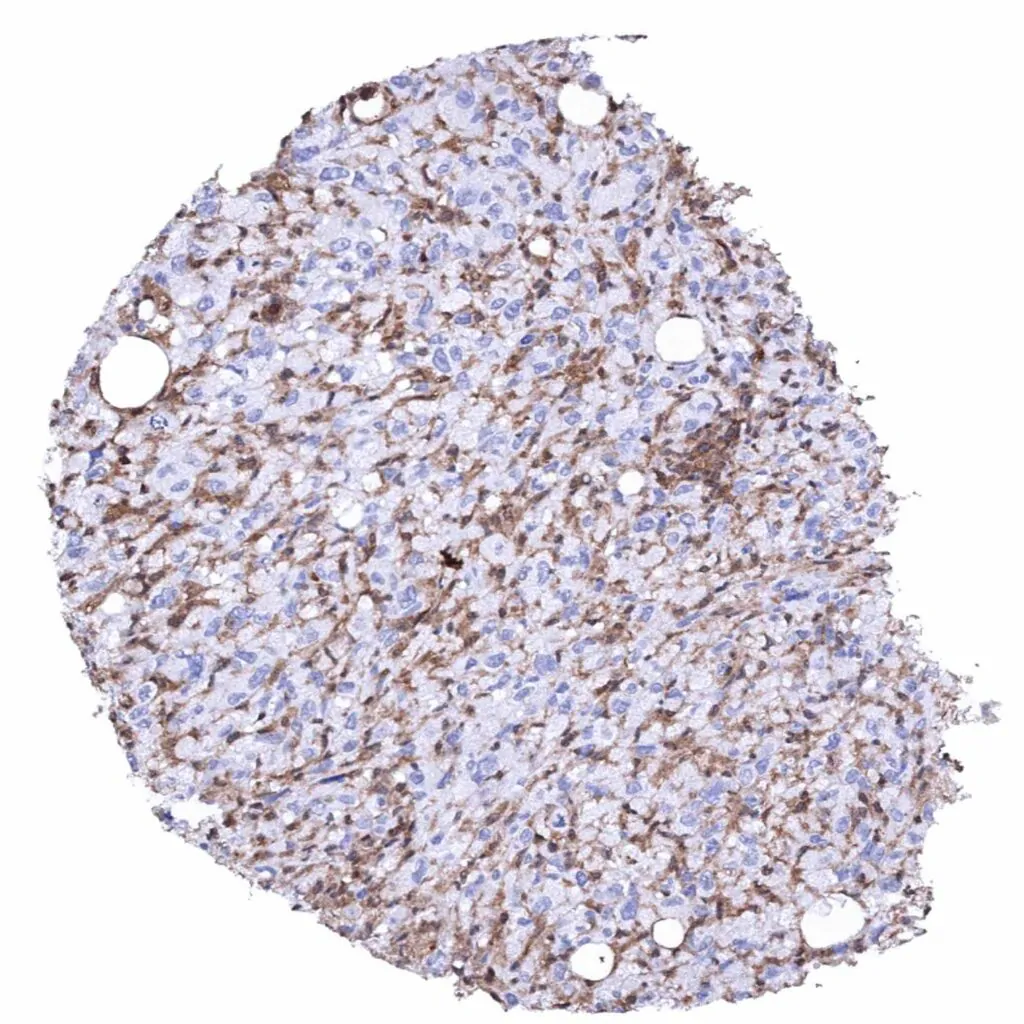

Appendix – Neuroendocrine tumor with complete absence of MTAP staining in tumor cells